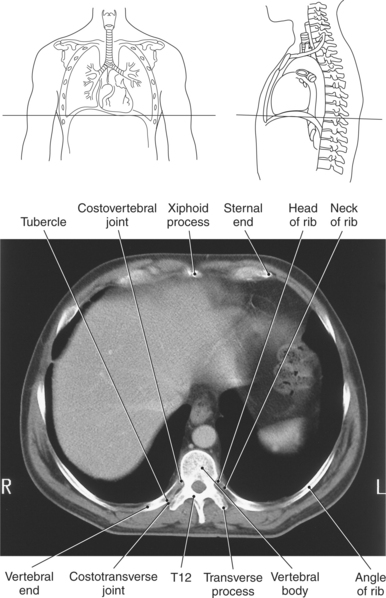

Forming the lateral borders of the thoracic cage are the 12 pairs of ribs. The spaces between adjacent ribs are referred to as the intercostal spaces. All 12 pairs of ribs articulate posteriorly with the thoracic spine. The ribs consist of a head, neck, tubercle, and body (Figures 6.7 and 6.8). The facets of the head of the rib articulate with the vertebral bodies at the costovertebral joints, whereas the facets of the tubercles articulate with the transverse processes of the vertebrae to form the costotransverse joints. The first 7 pairs of ribs (true ribs) articulate anteriorly with the sternum by costal cartilage. The lower 5 pairs of ribs are considered false ribs because they do not attach directly to the sternum. The costal cartilage of the eighth, ninth, and tenth ribs attach to the costal cartilage of the seventh rib. The eleventh and twelfth ribs are considered floating because they attach only to the thoracic vertebrae and contain no neck or tubercle, just vertebral and sternal ends (Figure 6.2).

There are two openings, or apertures, associated with the bony thorax. The superior aperture is formed by the first thoracic vertebra, first pair of ribs and their costal cartilages, and manubrium. This aperture, known as the thoracic inlet, allows for the passage of nerves, vessels, and viscera from the neck into the thoracic cavity. The inferior aperture is much larger and is made up of the twelfth thoracic vertebra, twelfth pair of ribs and costal margins, and xiphoid sternal junction. This aperture is known as the thoracic outlet (Figures 6.2, 6.5, and 6.8).